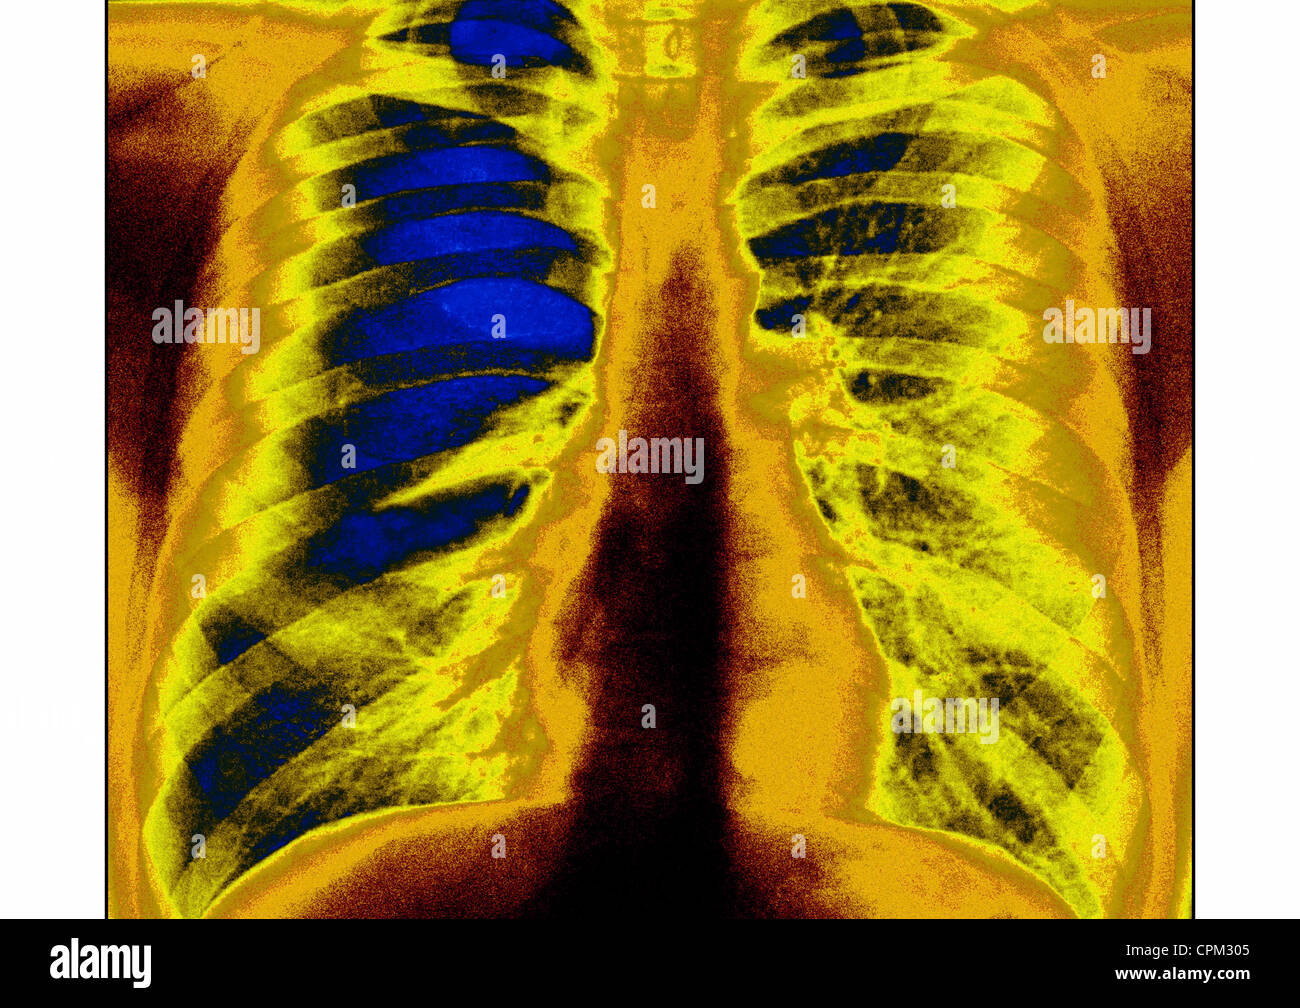

From www.sciencephoto.com

Asthma, Xray Stock Image C010/7553 Science Photo Library Can Asthma Be Seen In A Chest X Ray although bronchial thickening, hyperinflation, and focal atelectasis suggest asthma when they are present, chest radiographs obtained during. the classical symptoms of asthma are wheeze, shortness of breath, chest tightness or difficulty breathing and cough. Can Asthma Be Seen In A Chest X Ray.